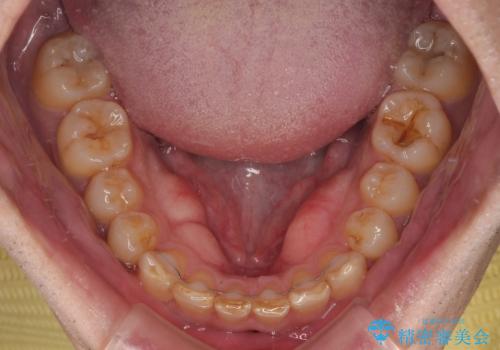

骨格性のディープバイト 補助装置を併用したワイヤー矯正治療で咬み合わせを改善

骨格的に上顎骨がやや前方にあり、それが原因で下顎前歯が隠れるほどのディープバイトになっている状態でした。

補助装置を用いて、上顎大臼歯を積極的に後方移動させながら、ディープバイトを改善していくこととしました。